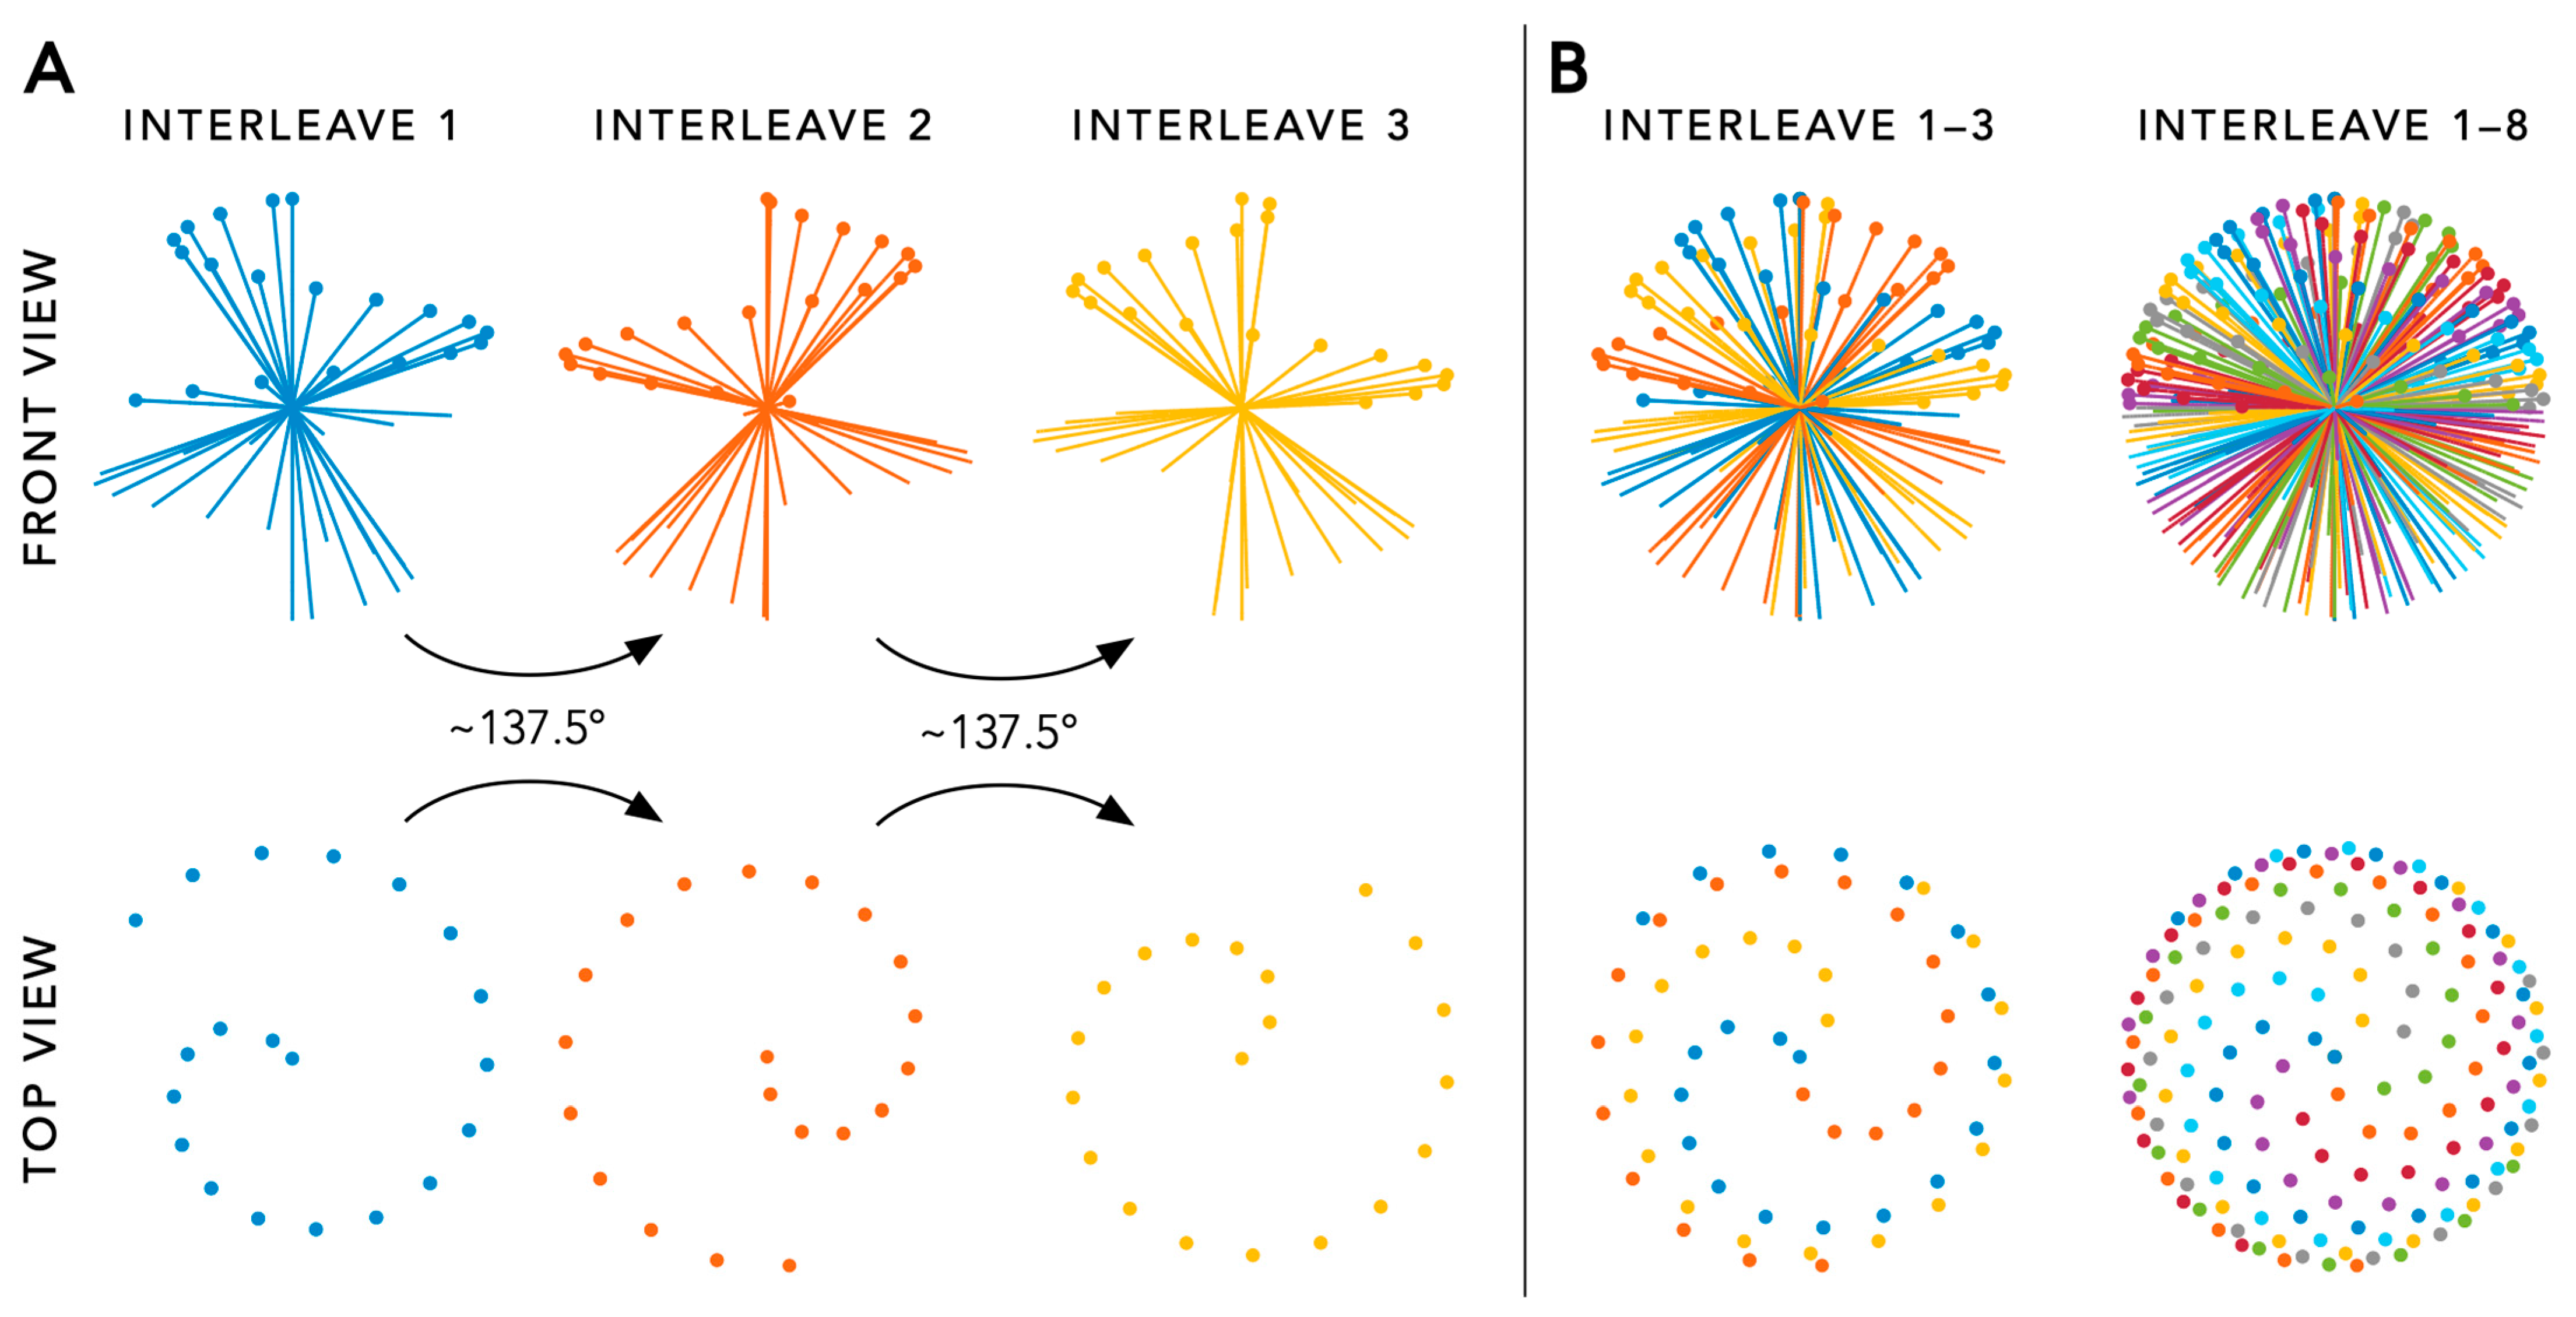

3.1. Acquisition